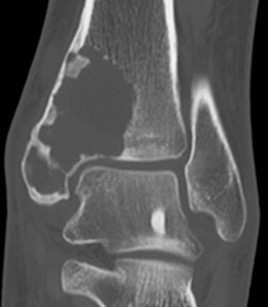

CT

ABC medial clavicle